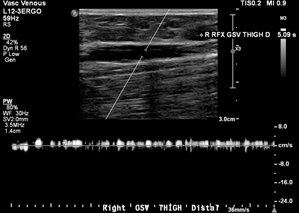

Case: 35F presented with painful right posteromedial thigh and knee vein, concerned for thrombosis given history of DVT in both parents. However, duplex ultrasound was unremarkable with no clots or reflux, and the patient was treated conservatively with compression stockings. She returned 6 years later noting leg fatigue worse at the end of nursing shifts. A repeat duplex performed 6 months earlier showed axial reflux in the right great saphenous and small saphenous veins (Figure 1).

Images showed questionable reflux and it was revealed that the study was performed in a moderate reverse Trendelenburg (RT) position. There was mild reflux at the SFJ in response to Valsalva and a long duration reflux in the thigh and leg in response to distal augmentation with the signal becoming intermittent distally.

Investigation: A low amplitude reflux could cause this pattern with gaps in reflux representing amplitude dipping below the detectable or filtered threshold. However, this could also represent a failure of RT position to generate sufficient downward pressure to achieve complete valve closure, which can result in a valve fluttering effect as blood passes through. We repeated the duplex ultrasound with the patient standing, and this was negative for reflux in any GSV segment.

Discussion: Optimal assessment of venous reflux with duplex imaging requires upright positioning. Tthis serves as a reminder that supine and even RT positioning can cause false positive results in addition to false negatives. Steep RT can provide accurate results and ease the ergonomic burden on technologists, but any questionable results should be double-checked in the standing position.